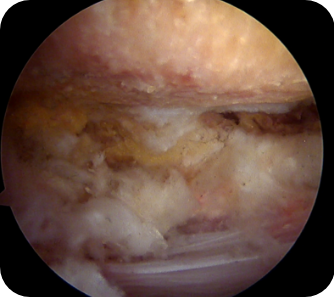

회전근개 질환, 오십견, 어깨 탈구 등 어깨 질환은 어깨의 통증과 고통을 야기합니다. 어깨 관절내시경 수술은 관절 질환이 의심되는 부위를 1cm 미만으로 최소절개한 뒤, 내시경 카메라와 수술 기구를 관절 내부에 삽입해 질환을 진단하고 치료하는 수술입니다. 화면을 통해 병변 부위를 직접 확인할 수 있어 손상 정도에 따라 파열된 힘줄을 봉합하거나 염증을 제거할 수 있습니다. CT나 MRI 등의 진단으로 잘 보이지 않던 곳까지 내시경을 삽입할 수 있어 적용 범위가 점점 넓어지고 있는 추세입니다.

- 회전근개 질환이 있는 경우